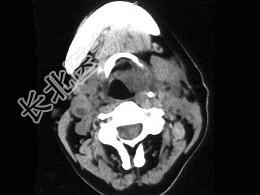

- 单项选择题女,54岁, 喉部异物感约3个月,PE: 左侧声带固定,可见肿物, CT如图,最可能的诊断是 ( )